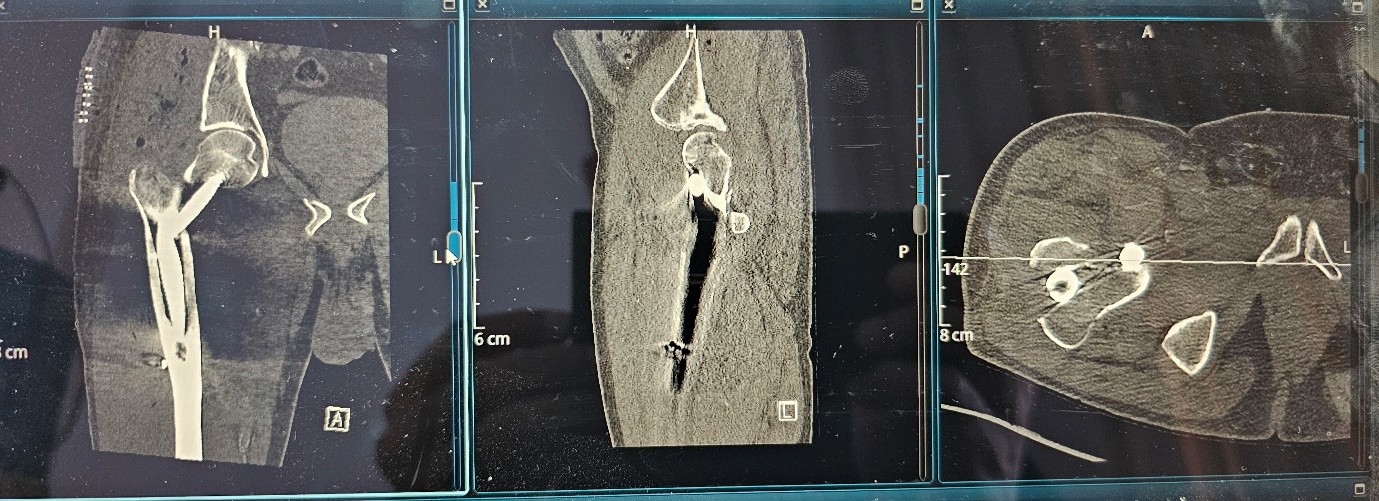

Multidisciplinary Review and Management Plan:

The case was reviewed in a multidisciplinary orthopedic surgery meeting. Given the evidence of mechanical failure, the decision was made to proceed with revision surgery.

Planned Revision:

Anatomical fracture reduction

Use of a medial-posterior nail entry point

Placement of the cephalic screw in a central–central position within the femoral head to optimize mechanical stability

Revision surgery :

Fig 6

Fig 7

Figure 6

Figure 7